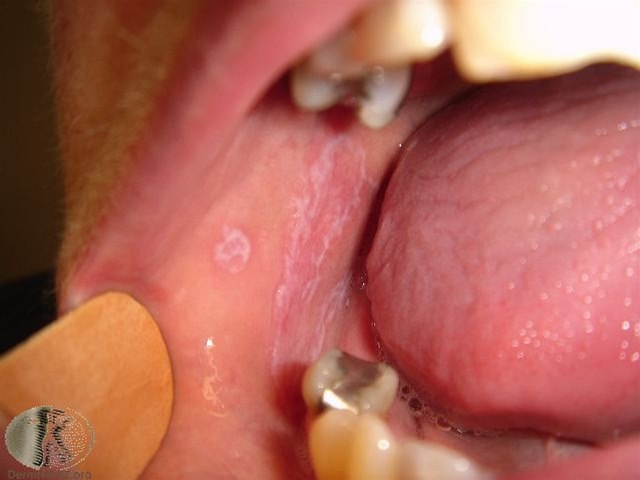

Die Veränderungen der Schleimhäute in der Mundhöhle können unterschiedliches Aussehen aufweisen. Sie treten meist beidseitig auf. Am häufigsten zeigt sich die Erkrankung als ein Netz von weißen Linien (netzartige Form) oder Flecken an der Innenseite der Wangen oder auf der Zunge. Gleichzeitig können in der Mundhöhle rote Bereiche und/oder wunde Stellen (erosive Form) vorkommen. Die netzartige Form ist am leichtesten zu erkennen und verursacht am wenigsten Beschwerden. Die erosive Form ist dagegen am schmerzhaftesten. Schleimhautveränderungen können auch auf dem Zahnfleisch, den Lippen, dem Mundboden und am Gaumen vorkommen. Schmerzen und brennende Beschwerden können auftreten. Die Beschwerden verschlimmern sich häufig nach dem Essen und Trinken.